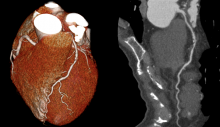

In this webinar, leading healthcare experts will discuss how observation, interviews, and experimentation can help the industry form a better understanding of current customer needs and pain points within cardiovascular imaging. Having clinicians involved in the product-design process has led to the complete rearchitecting of a next-generation hemodynamics solution.

Using a real-world scenario, we’ll share a clinician’s experience working with behavioral science and product-development teams, provide an understanding of how they’re using hemodynamics today, and get their thoughts on the future of imaging and hemodynamics.

What a next-generation hemodynamics system can do to keep pace with new technology innovations in cardiovascular care and increasing clinical demands.